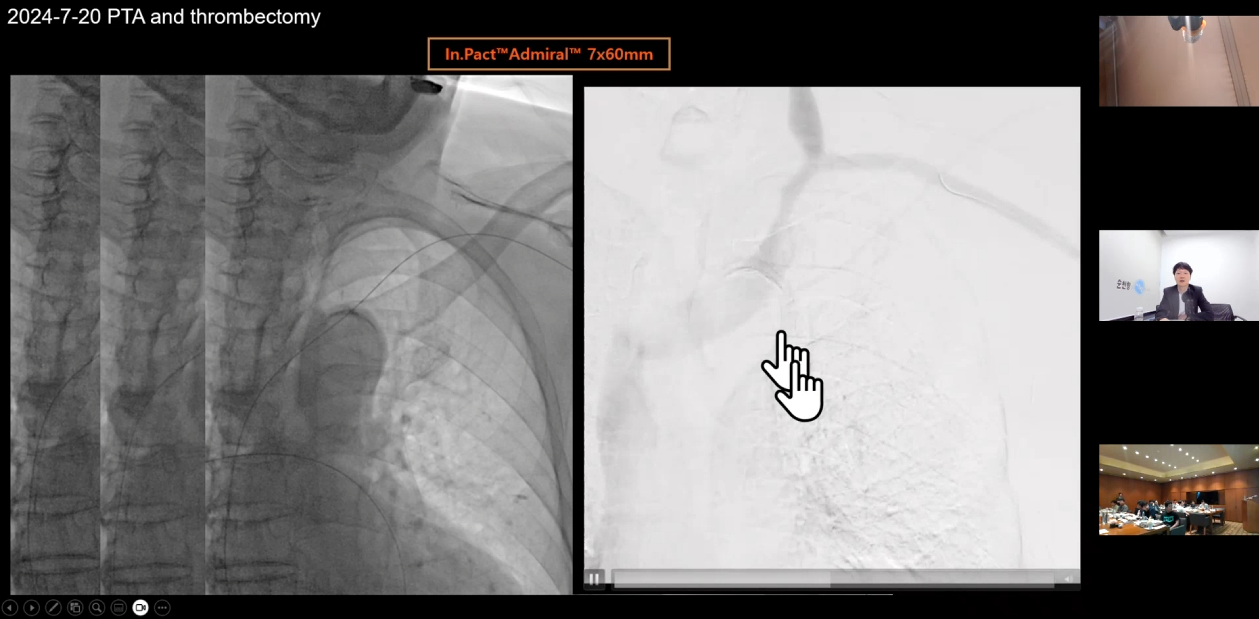

권요한 원장님은 'Can a DCB be a GAME changer?'라는 주제로

DCB에 대한 문헌 검토와

투석혈관 치료에서 DCB가 어떻게 사용되는지

시술 사례와 함께 치료 전략을 공유했습니다.